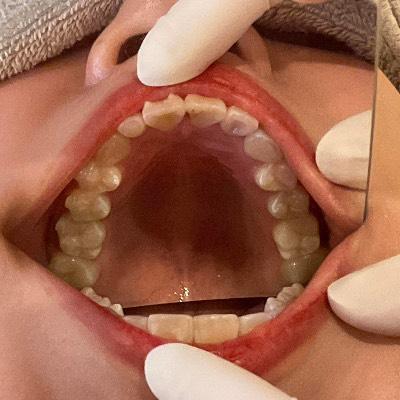

CASE 13

BEFORE

▶

AFTER

30代男性。「タバコのヤニやコーヒーなどの着色汚れ(ステイン)が気になる」「歯の裏側までしっかり綺麗にしたい」というご希望で来院。毎日の歯磨きや、通常のクリーニングでは落としきれない頑固な汚れにお悩みでした。